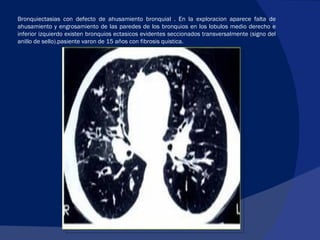

Bronquiectasias con defecto de ahusamiento bronquial . En la exploracion aparece falta de ahusamiento y engrosamiento de las paredes de los bronquios en los lobulos medio derecho e inferior izquierdo existen bronquios ectasicos evidentes seccionados transversalmente (signo del anillo de sello).pasiente varon de 15 años con fibrosis quistica.

Bronquiectasias con defectode ahusamiento bronquial . En la exploracion aparece falta de ahusamiento y engrosamiento de las paredes de los bronquios en los lobulos medio derecho e inferior izquierdo existen bronquios ectasicos evidentes seccionados transversalmente (signo del anillo de sello).pasiente varon de 15 años con fibrosis quistica.